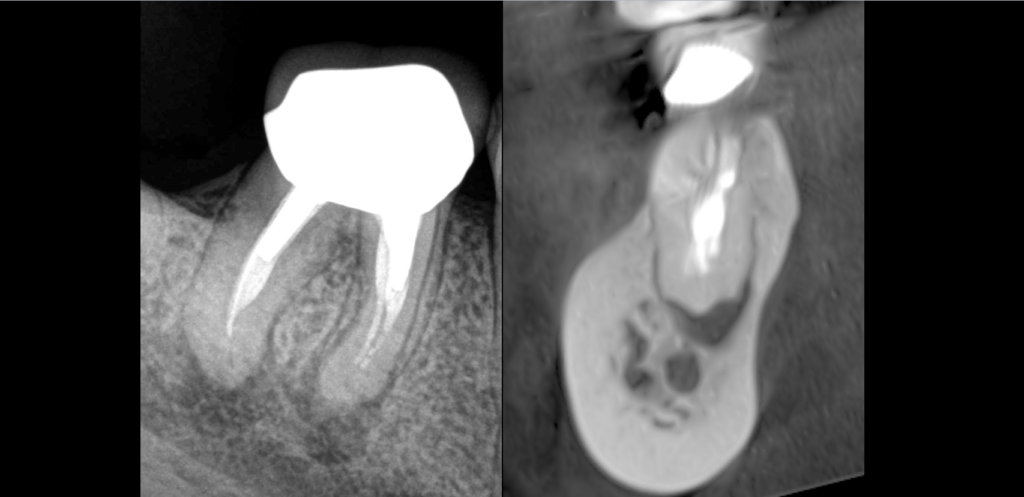

🔍 𝐏𝐮𝐥𝐩𝐞 𝐩𝐫𝐞́𝐜𝐞́𝐝𝐞𝐦𝐦𝐞𝐧𝐭 𝐭𝐫𝐚𝐢𝐭𝐞́𝐞, 𝐩𝐚𝐫𝐨𝐝𝐨𝐧𝐭𝐢𝐭𝐞 𝐚𝐩𝐢𝐜𝐚𝐥𝐞 𝐬𝐲𝐦𝐩𝐭𝐨𝐦𝐚𝐭𝐢𝐪𝐮𝐞 (lésions apicales des racines M et D).

⚠️ La microchirurgie endodontique ne pouvant être réalisée en raison de l’épaisseur d’os en vestibulaire (de la corticale jusqu’à l’apex !).